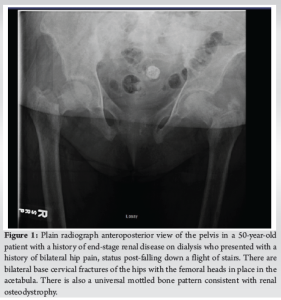

A 50-year-old female with a past medical history of ESRD on dialysis, coronary artery disease (CAD), hypertension, and dyslipidemia presented to the emergency department with bilateral hip pain after she had sustained a fall while at home just before arrival. Per Emergency Medical Services, the patient fell down a full flight of stairs. The patient states that she felt a “pop” with subsequent pain in the hips and has been unable to move her hips since. On physical examination, the patient was in no acute distress and was awake, alert, and oriented ×3 with no evidence of altered mental status. She had appropriate tenderness over the hips bilaterally. The patient was neurologically and vascularly intact with palpable dorsalis pedis pulses, warm toes, and intact sensation. An anteroposterior (AP) view X-ray of the pelvis (Fig. 1) and frog-leg lateral views of each hip individually were ordered. Universal mottled bone patterns consistent with renal osteodystrophy/secondary hyperparathyroidism with erosive and destructive changes on both sides of the pubic symphysis were visualized. Bilateral basicervical fractures of the hips were also noted. The patient also had a computerized tomography (CT) scan without contrast of the pelvis, which revealed acute transcervical fractures through the proximal femurs bilaterally and an acute displaced fracture of the left greater trochanter. Severe degenerative changes at the pubic symphysis with probable brown tumors in the pubic bone and L5 and S1 vertebral bodies were also noted, which were consistent with the X-ray findings. The patient also had a CT of the head without contrast performed, which did not reveal any significant findings.

28 days after admission and initial presentation, the patient consented to bilateral non-cemented hemiarthroplasties performed through the direct anterior approach with the patient supine. The surgeon felt that less patient movement in this approach (as compared to the lateral decubitus position) would make the surgery more efficient due to decreased blood loss and a lack of available blood products. On the right, a size 7 collared stem minus head with a 51 bipolar component was used. On the left, a size 7 collated stem plus 0 head with a 52 bipolar component was used. Both implants were Medacta. Bilateral release of hip contractures with capsulotomies with removal of multiple bone fragments was performed. Femoral head bone biopsies were also taken. The tensor fascia latae was closed with a #1 Vicryl followed by 0 Vicryl staples. A Prevena vacuum dressing was applied with excellent suction. There were no complications during the procedure as the patient was successfully extubated and transferred to the recovery room. On post-operative day 7, the patient was able to bear weight after sitting at the edge of the bed. The patient reported 8/10 right knee pain but could not give a numerical value for back pain. The patient agreed to participate in physical therapy upon discharge. Post-operative AP X-rays of the pelvis can be seen in (Fig. 3).